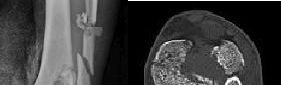

Figure 1 is the radiograph and Figure 2 is the CT image of a 45-year-old woman who fell about 20 feet off her balcony. These images show an isolated, open injury with a 3-cm open medial wound.

The best delayed definitive surgical fixation plan would include

Discussion: The timely administration of antibiotics has been shown to be the best initial treatment to reduce the incidence of infection following an open fracture. Life threatening injuries must first be addressed. But in this isolated open pilon fracture, antibiotics should be initiated early along with tetanus prophylaxis. Reduction and splinting would stabilize the fracture but these interventions should follow antibiotic coverage. Emergency department irrigation is controversial. Closed reduction and splinting, external fixation, CT scan, and delayed open reduction internal fixation would be the preferred sequence of management. External fixation to provide provisional limb stabilization would be indicated in this length unstable C type injury to provide soft tissue stabilization and prevent further chondral injury. Splinting alone would not prevent shortening and would not allow soft tissue recovery. CT scans prior to limb stabilization are not warranted because the patterns make more sense after the restoration of gross length, rotation and alignment in the external fixator. Initial fibular fixation is also not recommended in this case because the location of incisions could affect the definitive surgical tactic. In this multi-fragmentary fibular injury, anatomic reduction would be challenging and malreduction could occur and influence subsequent reconstructions. Delayed open reduction internal fixation is ideal after the resolution of soft tissue swelling.